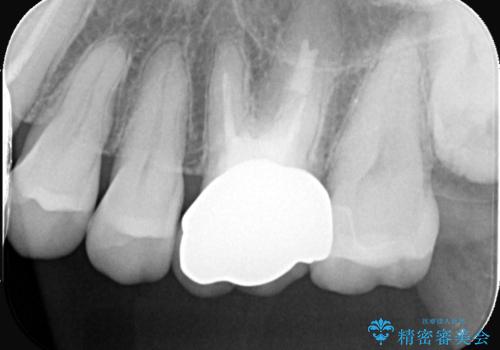

- 主訴:昔入れた銀の詰め物を白い物に替えて金属を無くしたい。

審美性、適合性の観点からセラミックインレーでのやり替えとなりました。

保険適用のメタルインレーを除去した際、下に広がっているカリエスも除去し形成印象を行いました。

セラミックインレーセット時はラバーダム防湿を行っています。